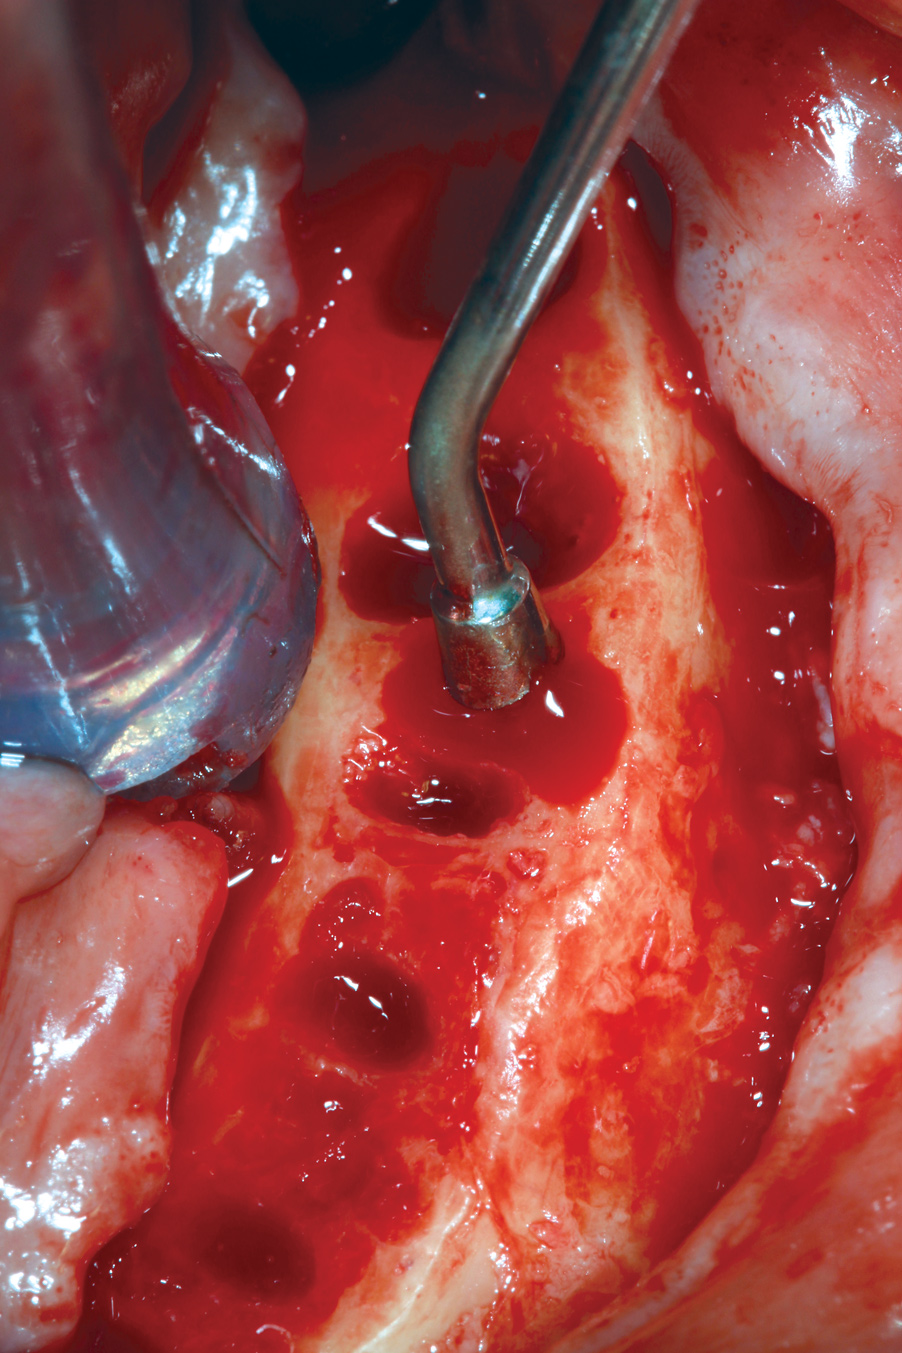

Hemorrhage From Osseous Nutrient Canals

All-on-4–style treatment typically involves reduction of alveolar and/or basal bone (Figure 9) to achieve adequate restorative space for both the interim and final prostheses.25-27 During reduction of this bone, exposure of intraosseous nutrient canals28,29 may lead to hemorrhaging that may obscure visualization of the surgical field. If left uncontrolled, hemorrhaging from nutrient canals can become significant, resulting in excessive blood loss. It is not uncommon to encounter multiple concurrently hemorrhaging intraosseous nutrient canals, especially during mandibular bone reduction.

When faced with this situation, the author uses the blunt end of a handheld instrument, such as a Woodson instrument (Figure 10), to put heavy pressure on bone directly adjacent to the bleeding nutrient canal. This pressure typically deforms the adjacent bone to a point at which it occludes the hemorrhaging. The author has encountered hundreds of hemorrhaging intraosseous nutrient canals and has never had this technique fail to achieve the desired results.

Fig 9. Alveolar bone reduction prior to dental implant placement in a mandibular All-on-4–style dental implant surgery.

Figure 9

Fig 10. Woodson hand instrument used to condense bone at the site of an intraosseous nutrient canal hemorrhage.

Figure 10